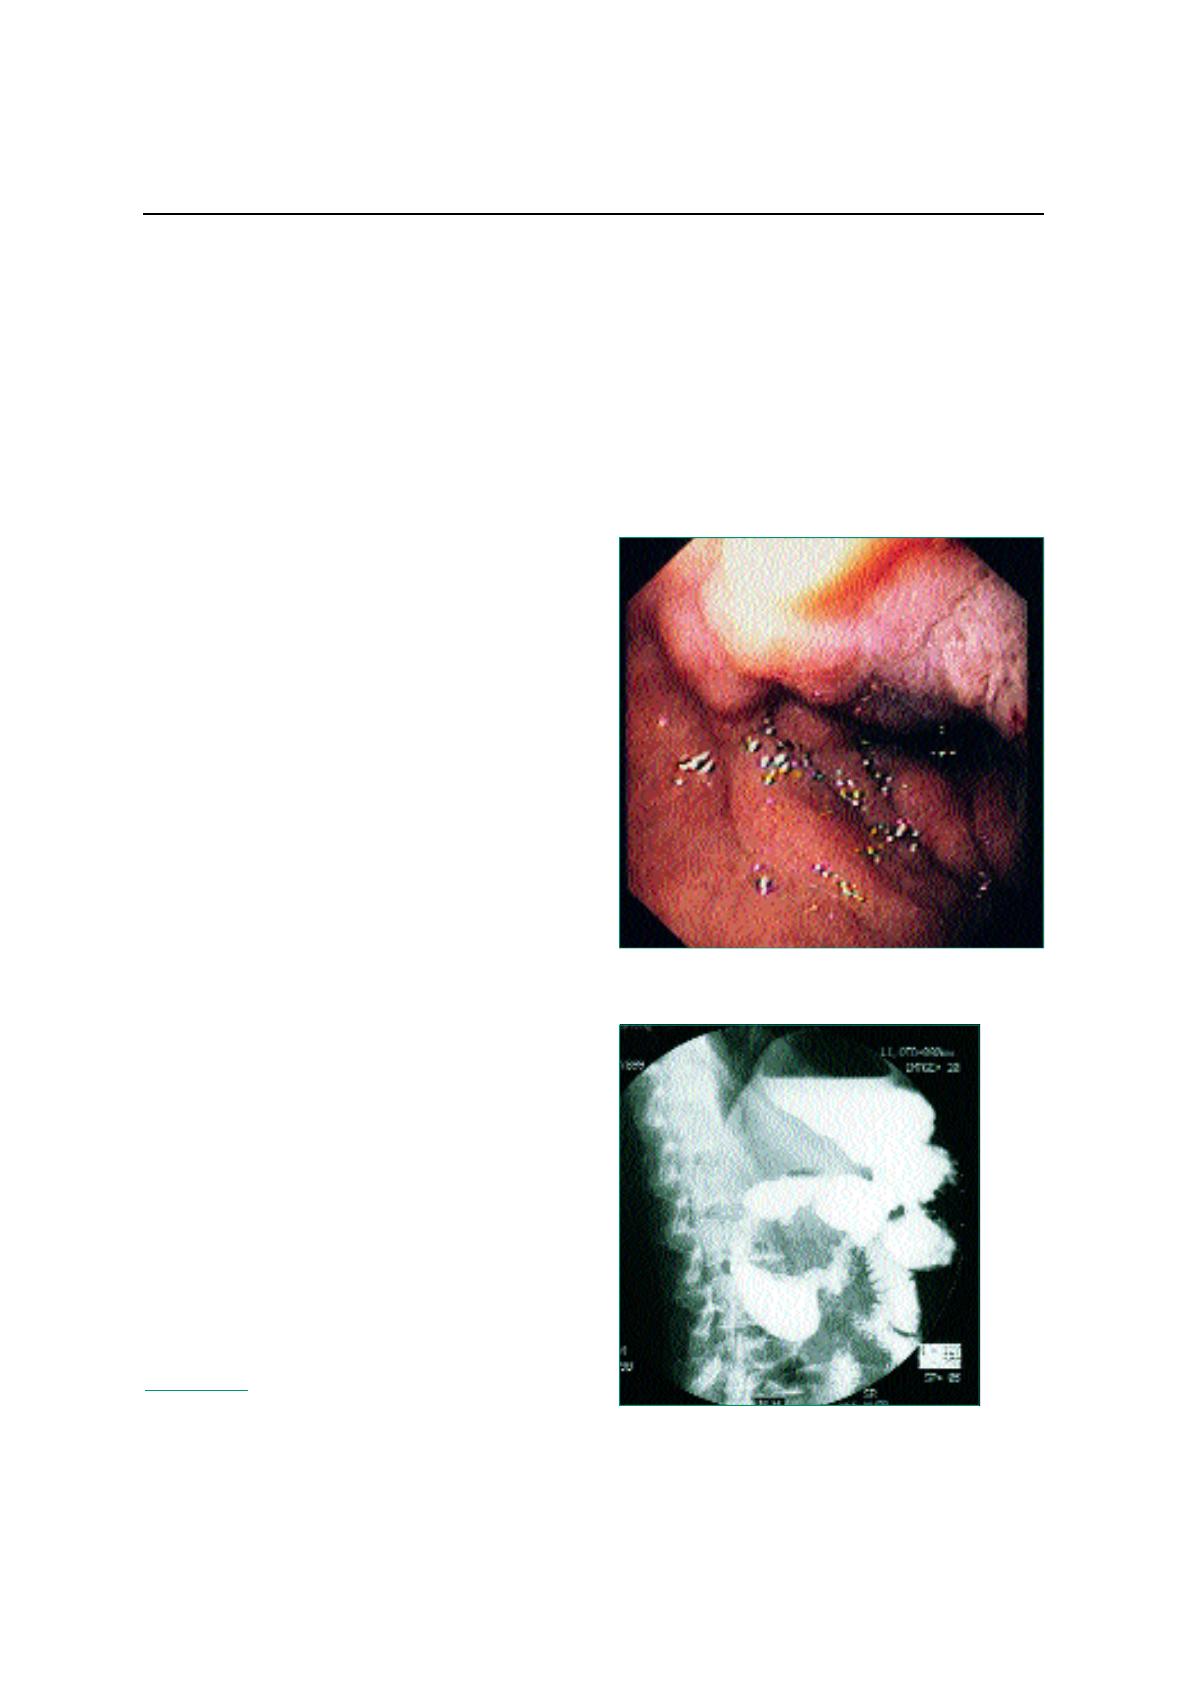

évidence de calcifications dans l'aire pancréatique. La gastro-

scopie montrait une sténose inflammatoire à la partie haute du

deuxième duodénum, franchie sans ressaut, hémicirconféren-

tielle (figure 1). Le transit œsogastroduodénal confirmait cette

sténose de la partie haute de D2 (figure 2). L'échographie abdo-

Figure 1.

Figure 2.